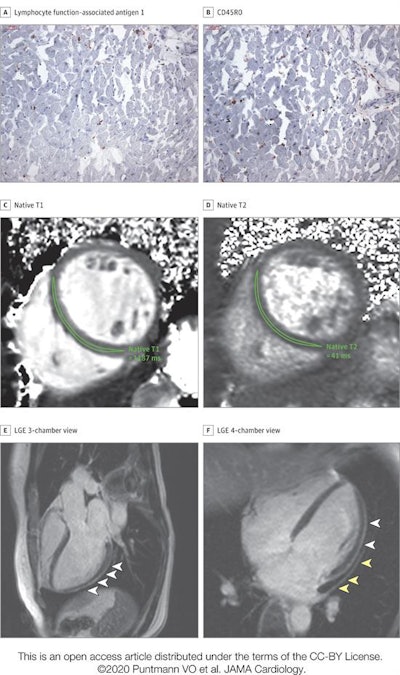

High-sensitivity troponin T level on the day of cardiac MRI was 17.8 pg/mL. The patient recovered at home from COVID-19 illness with minimal symptoms, which included loss of smell and taste and only mildly increased temperature lasting two days. There were no known previous conditions or regular medication use. Histology revealed intracellular edema as enlarged cardiomyocytes with no evidence of interstitial or replacement fibrosis. (A and B) Immunohistochemical staining revealed acute lymphocytic infiltration (lymphocyte function-associated antigen 1 and activated lymphocyte T antigen CD45R0), as well as activated intercellular adhesion molecule 1. (C and D) Cardiac MRI revealed enlarged volumes in myocardial mapping acquisitions, including significantly raised native T1 and native T2. (E and F) Pericardial effusion and enhancement (yellow arrowheads) and epicardial and intramyocardial enhancement (white arrowheads) were seen on late gadolinium enhancement (LGE) acquisition. Images and caption courtesy of JAMA Cardiology."The most prevalent abnormality [on cardiac MRI] was myocardial inflammation (defined as abnormal native T1 and T2 measures), detected in 60 patients recently recovered from COVID-19 ... followed by regional scar and pericardial enhancement," the group noted.